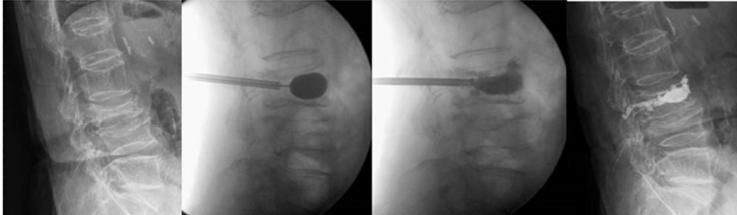

Kyphoplasty is a minimally invasive, image-guided procedure designed to stabilize vertebral fractures, relieve pain, and partially restore vertebral height.

It involves the insertion of a balloon within the vertebral body to create a cavity, followed by controlled injection of bone cement (PMMA), allowing better height restoration and reduced cement leakage compared to standard vertebroplasty.

Percutaneous transpedicular access under CT or fluoroscopic guidance

Balloon inflation within the vertebral body to create a cavity

- Controlled cement injection with real-time imaging